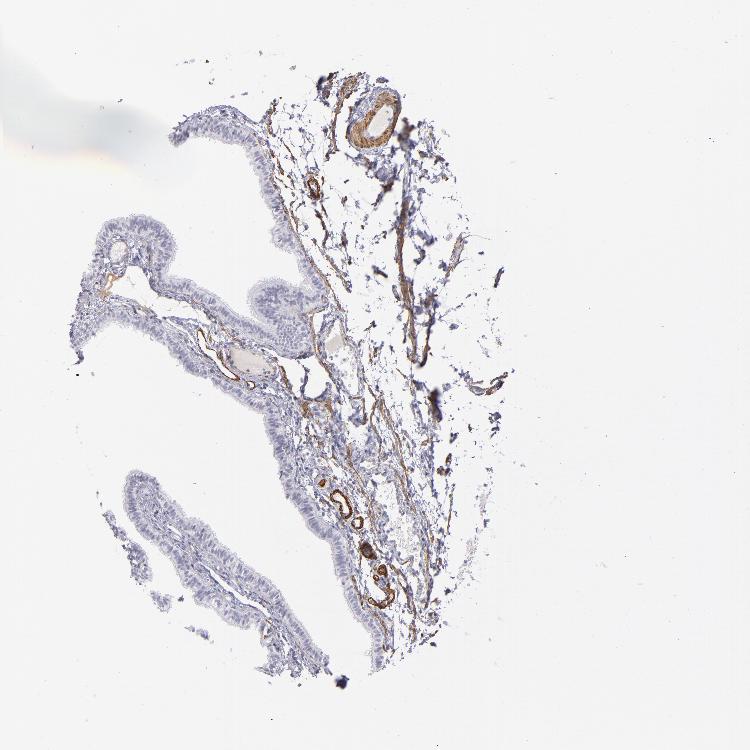

TISSUE PRIMARY DATA FALLOPIAN TUBE Show tissue menu

FALLOPIAN TUBE - Antibody stainingi

Antibody staining in the annotated cell types in the current human tissue is reported as not detected, low, medium, or high, based on conventional immunohistochemistry profiling in selected tissues. This score is based on the combination of the staining intensity and fraction of stained cells.

Each image is clickable and will lead to virtual microscopy that enables deeper exploration of all samples and also displays staining intensity scores, fraction scores and subcellular localization as well as patient and tissue information for each sample.

Antibody HPA014539Antibody HPA015310Antibody CAB002302

Glandular cells LowNot detectedNot detected